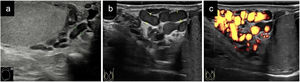

La mayoría de las veces, el seminoma se encuentra confinado al interior de la túnica albugínea. Suele presentarse ecográficamente como una lesión homogénea, hipoecogénica e intratesticular, de aspecto numular. Ocasionalmente es multinodular (vídeo 1) o se presenta como una lesión focal con márgenes lobulados (figs. 2a y b).

Cortes longitudinales de masas testiculares: a) Masa intratesticular homogénea e hipoecogénica (medida en ejes longitudinal y anteroposterior con línea discontinua amarilla) con diagnóstico anatomopatológico de seminoma; b) Imagen a con captación Doppler color; c) Masa que ocupa la práctica totalidad del teste (medido en ejes longitudinal y anteroposterior con línea discontinua amarilla) hipoecogénica con diagnóstico anatomopatológico de linfoma.

En varones mayores de 60 años, el tumor testicular maligno más frecuente es el linfoma, tratándose normalmente de un linfoma no Hodgkin que presenta un peor pronóstico. Suele ser en su mayoría unilateral y la ecografía nos muestra un testículo de mayor tamaño con un parénquima difusamente hipoecogénico (fig. 2c) con aumento del flujo sanguíneo, o lesiones hipoecogénicas multifocales.